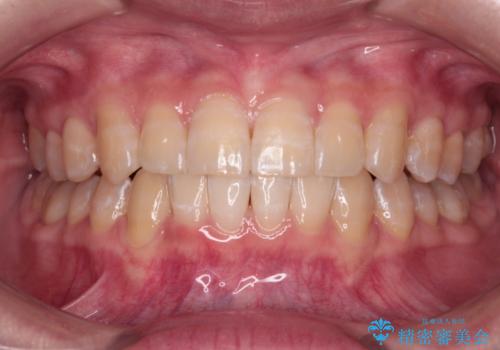

歯列以外に、上顎左右側切歯が矮小歯であり、上顎4前歯は失活していたため、矯正治療で歯列を整えるとともに上顎前歯の幅を調整し、矯正治療後にオールセラミッククラウンにて審美歯科治療を行うこととしました。

下顎の小臼歯を移動しきるのに2年弱の期間を要することとなり、補綴治療も合わせて2年半ほどの治療期間となりました。

口元の印象が大きく改善し、患者様には大変満足していただけました。